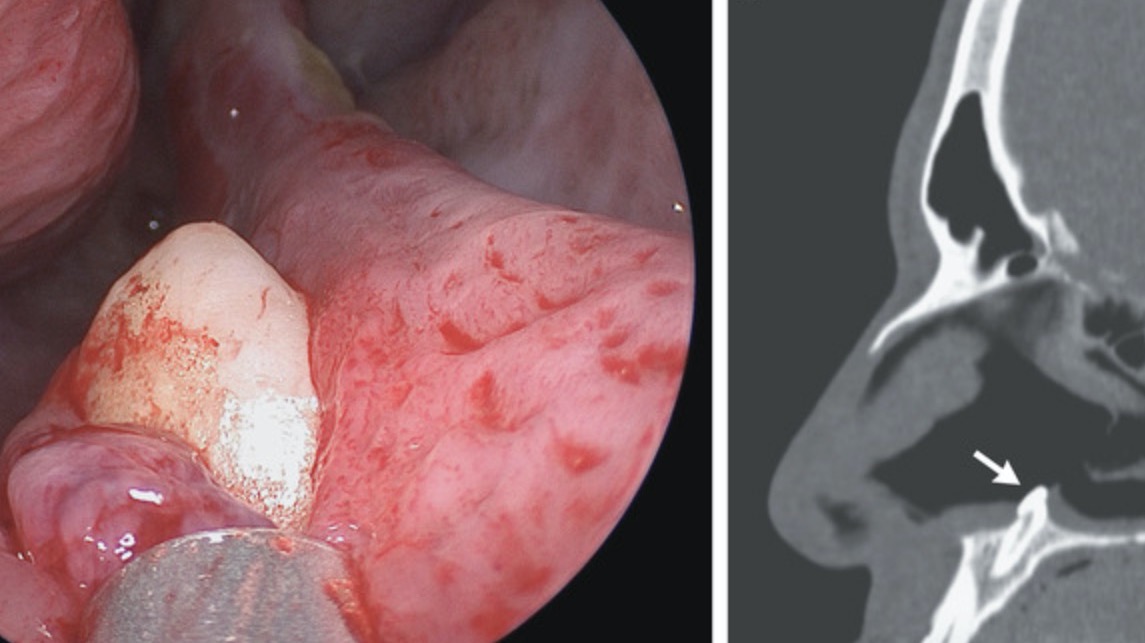

L’examen physique aurait ensuite révélé un septum dévié (le cartilage au milieu qui sépare une narine de l’autre), ainsi qu’une obstruction osseuse et une déchirure de deux centimètres de long vers l’arrière du septum. Comment l’expliquer ? En regardant d’un peu plus près au moyen d’un fibroscope (tube souple formé de fibre optique qui permet de voir à distance), les médecins ont alors isolé la coupable : une « masse blanche dure » dépassant du sol de la narine.

Un tomodensitogramme a ensuite confirmé qu’il s’agissait bel et bien d’une dent ectopique. En anatomie, il s’agit d’un terme un peu fourre-tout visant à souligner le placement anormal d’une partie du corps.

Notez que les dents ectopiques ne sont pas systématiquement traitées. En effet, certaines peuvent se développer normalement après avoir défié les « consignes anatomiques ». Selon leur position, elles peuvent également être ajustées au moyen d’appareils orthodontiques. Ici, les médecins ont finalement opté pour une ablation chirurgicale. La dent mesurait quatorze millimètres de long. Depuis, l’homme peut enfin respirer normalement.